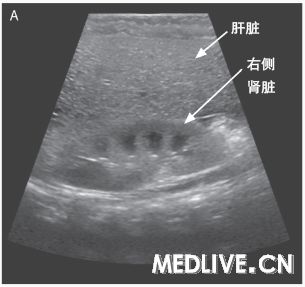

图1 腹部成像检查 右肝叶矢状面超声图像(图A)显示,与邻近的肾脏相比,肝实质回声增强,这与脂肪浸润(的表现)一致。腹部轴向计算机体层摄影图像(图B)显示,弥漫性肝脏密度降低,这也与脂肪浸润(的表现)一致。

奥托·拉帕利诺医师:入院时进行的腹部超声显示肝实质回声弥漫性增强,符合脂肪浸润,没有局灶异常,并且胆囊周围有少量液体(图1A)。为了进一步评估肝脏而进行的腹部CT检查显示,肝实质脂肪性衰减,轻度肝肿大,以及胆囊周围有少量液体(图1B)。